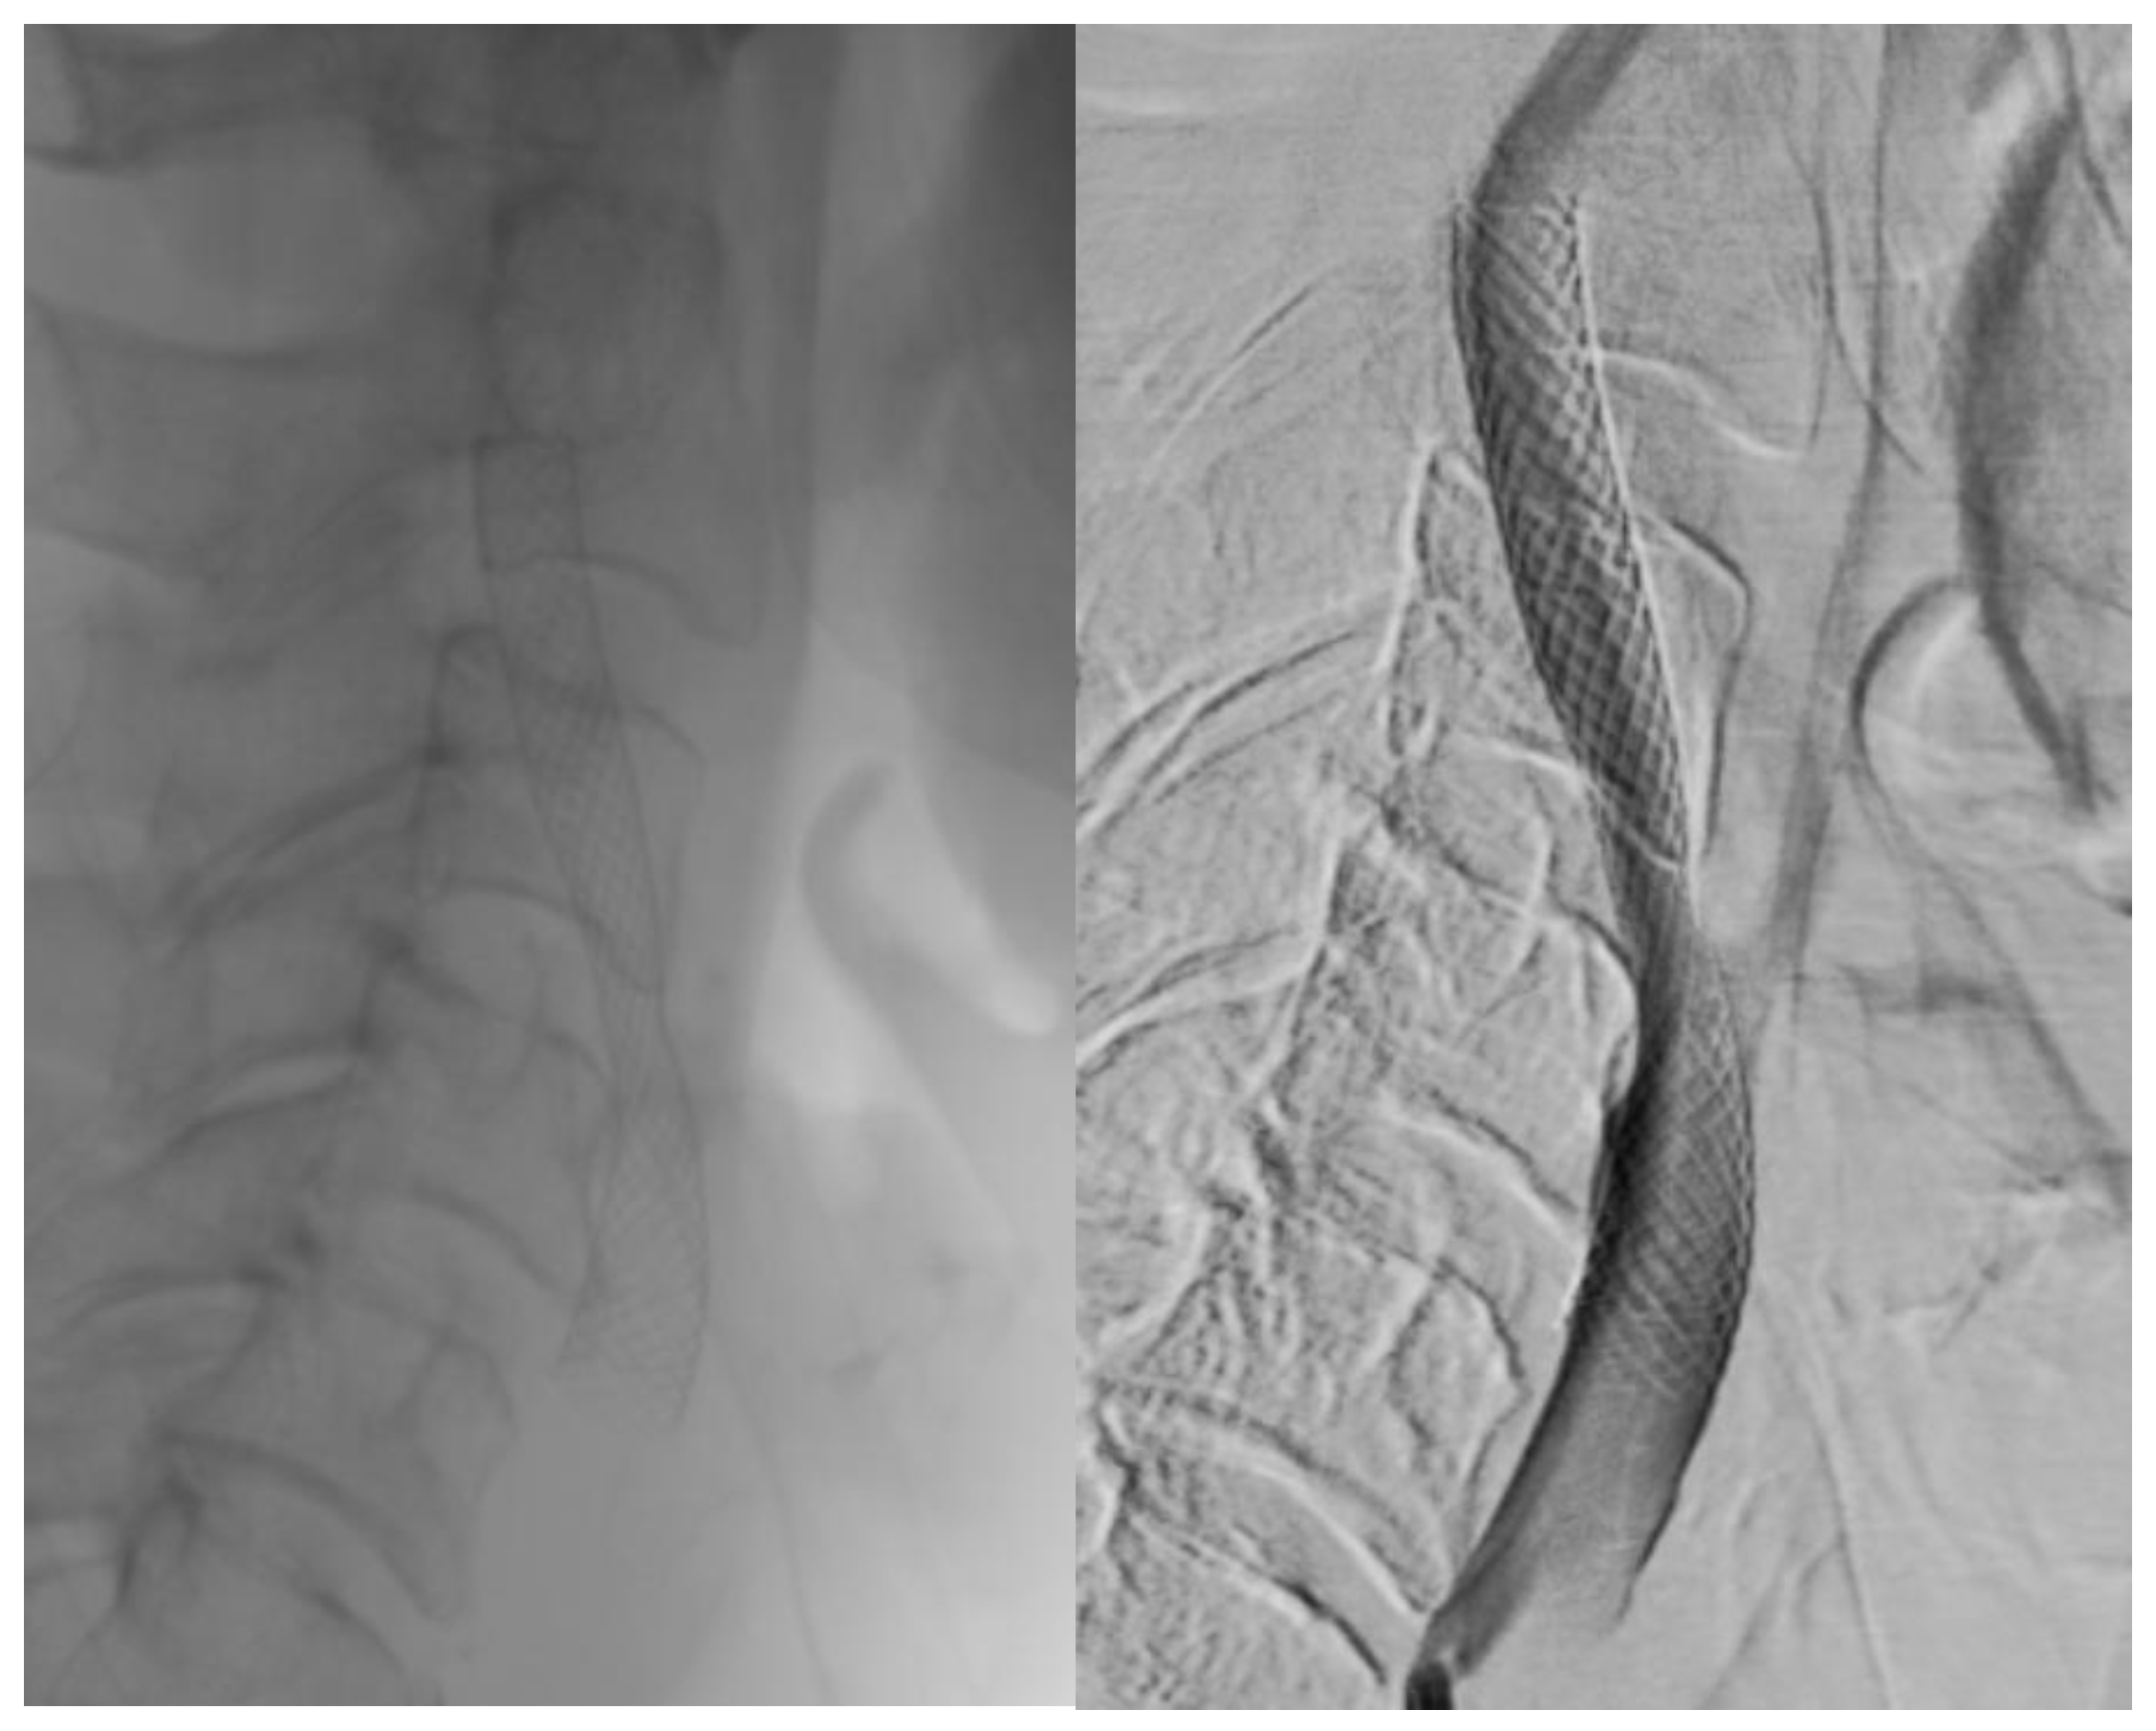

Visual differences between single- and double-layer carotid stents as seen during the angiography procedure are illustrated in Figure 2, Figure 3 and Figure 4.

Figure 1. Single-layer micromesh stent (Wallstent-Boston Scientific).

Jcm 14 00888 g001